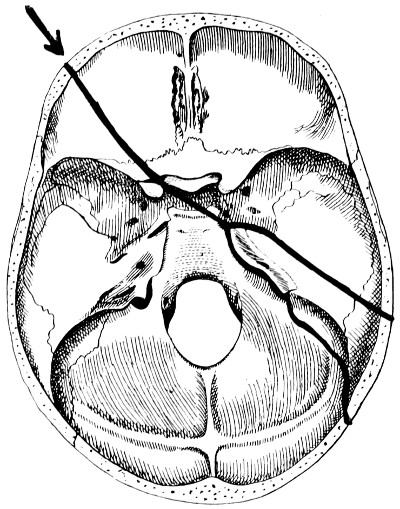

| 28. Illustrating the lines along which forces received on the vault are transmitted to the base | 69 |

| 32-37. The lines pursued by basic fractures | 83-8 |